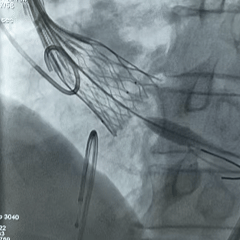

手术过程

左侧冠脉造影

右侧冠脉造影并行PCI

根部造影

可见瓣叶钙化,伴反流

TF21瓣膜0位初始释放

全展开后多角度根部造影:瓣膜深度形态合适,冠脉灌注良好,少量瓣周漏,选择解锁脱钩

脱钩后造影评估:瓣膜深度可,展开良好,少量瓣周漏

外周造影检查,血管无损伤